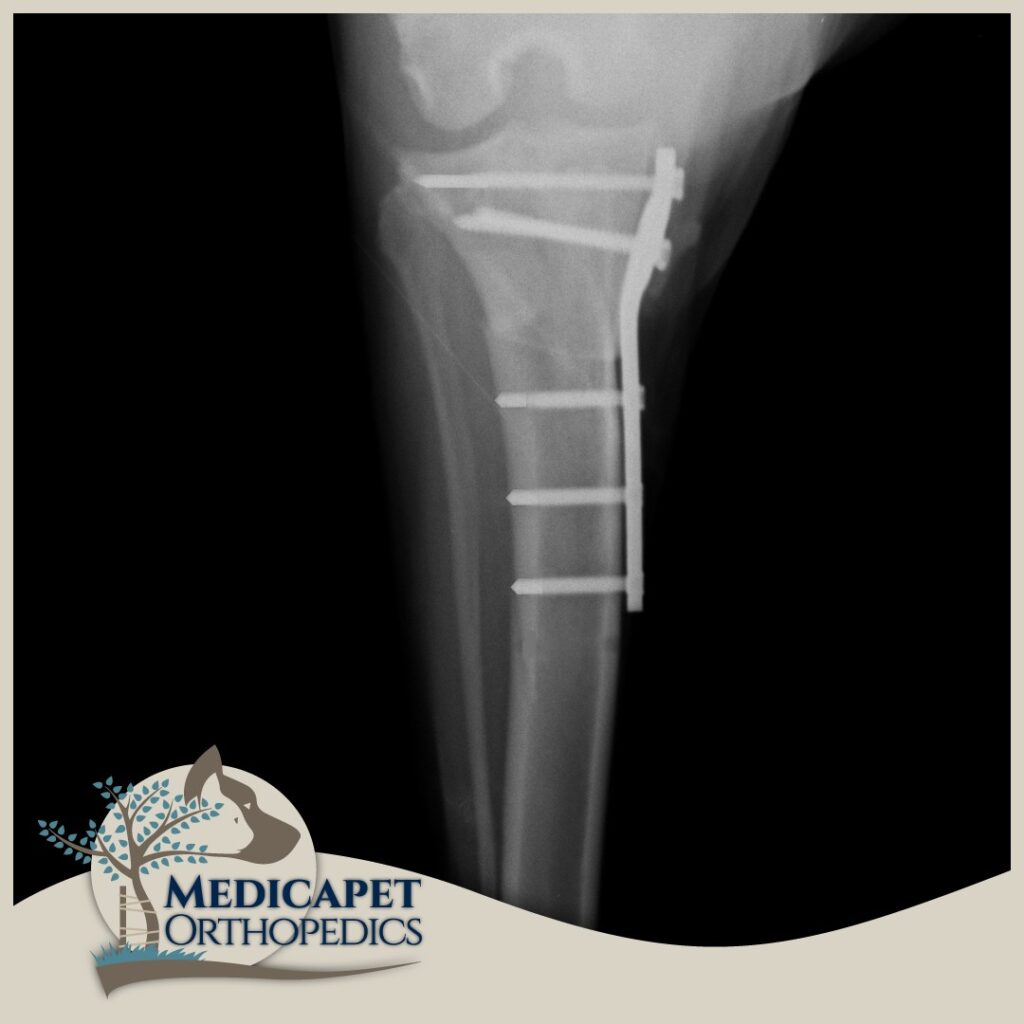

TTA – Tibia’nın ilerletilmesi

Bu ameliyat, TPLO ile aynı prensibi izler ve ön çapraz bağı gereksiz kılan bir geometrik ve biyomekanik bir değişikllik meydana getirir. TTA’nın ardındaki matematiksel prensipler, TPLO’nun ardındakilerden daha karmaşıktır; ancak temel prensip, quadriceps kas grubundan gelen çekiş yönünün değişmesinin, femur kemiğinin tibial plato eğiminden aşağı doğru kayma eğilimini nötralize eden diz eklemi boyunca bir kuvvet üretmesidir. Aslında, hem TTA hem de TPLO, tibial platoyu düz patellar tendona dik hale getirmeyi ve bunu yaparken femur kemiğinin tibia eğiminden aşağı doğru kayma eğilimini nötralize etmeyi amaçlar. Patellar ligament hasarı olan hastalarda TTA tekniği uygun olmayacaktır. Çünkü TTA tekniğini uygularken bu ligamentin çekme kuvvetinden faydalanılır.

Kemik iyileşmesinin bağ iyileşmesinden daha kolay ve hızlı olması sebebiyle, bu onarımlar hasarlı bağın değiştirilmesi için tasarlanan ameliyatlardan önemli ölçüde daha sağlamdır. En büyük pratik fayda, tüm köpeklerin kısa süre içinde ameliyat edilen uzuvda ağırlık taşımaya başlamasının beklenmesiyle, uzuv kullanımının çok güvenilir bir şekilde geri dönmesidir. TPLO ve TTA’nın mekanik avantajları, hızlı işleve dönüşle birleştiğinde, özellikle ağır köpekler, atletik hayvanlar, hafif aksama gösteren hayvanlar ve her iki diz eklemini de etkileyen ön çapraz bağ yaralanmaları olan hayvanlar için önemlidir. Her iki dizini aynı anda etkileyen ön çapraz bağ yaralanmaları olan bazı hayvanlarda, TPLO tek bir ameliyatta her iki diz eklemine uygulanabilir. Bağ değiştirme teknikleri kullanıldığında bu mümkün değildir.